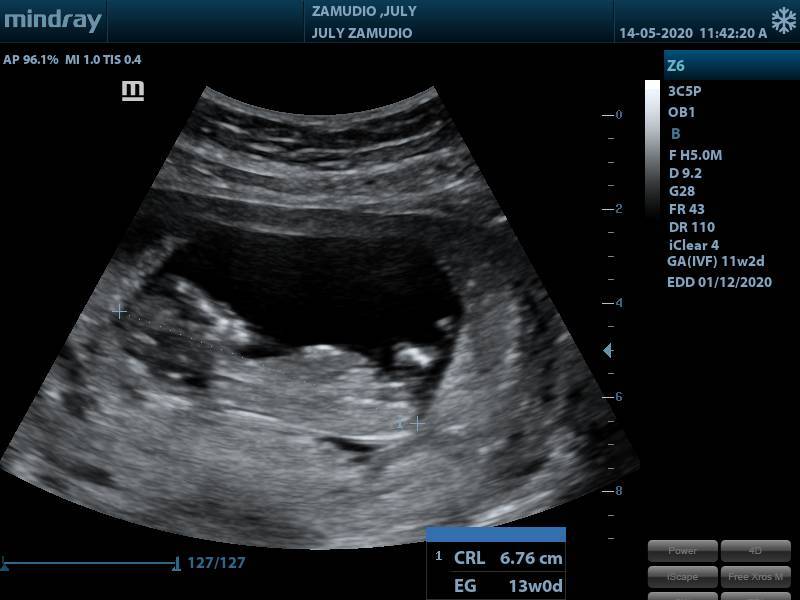

ULTRASON